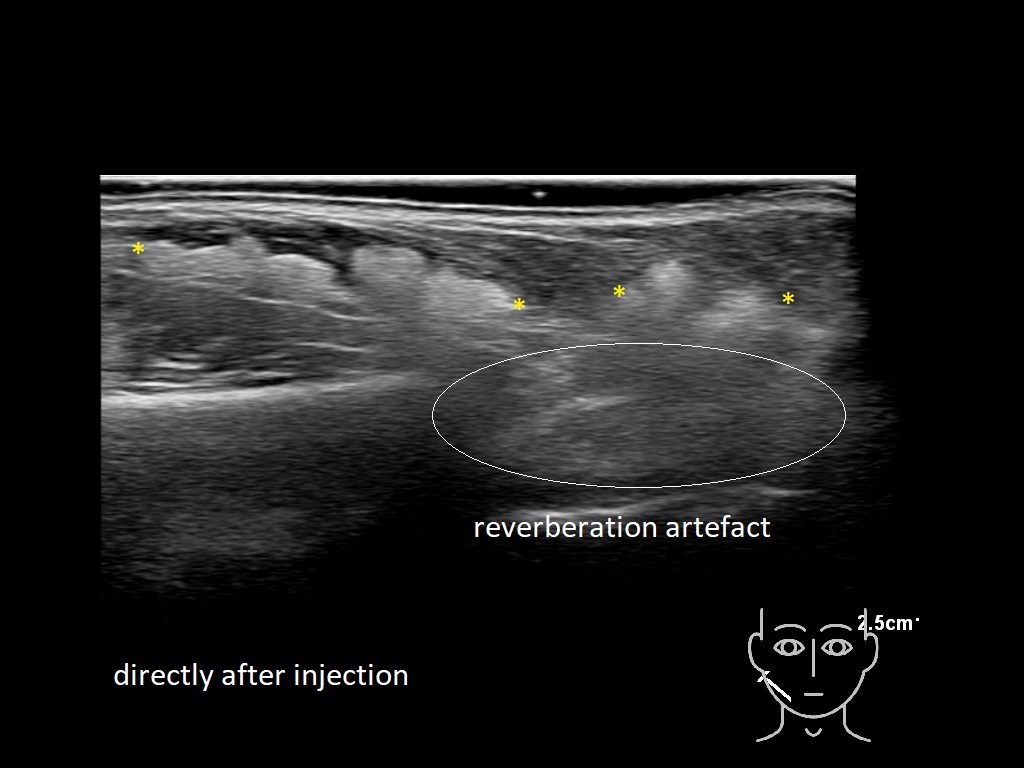

Draw in the second image below where the fillers are located. To check if your answer is correct, swipe the first image to the right.